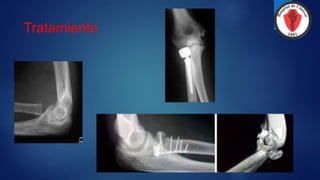

TRATAMIENTO

Son todas quirúrgicas, salvo la

denominada ¨bolsa de huesos¨ del

anciano osteoporótico